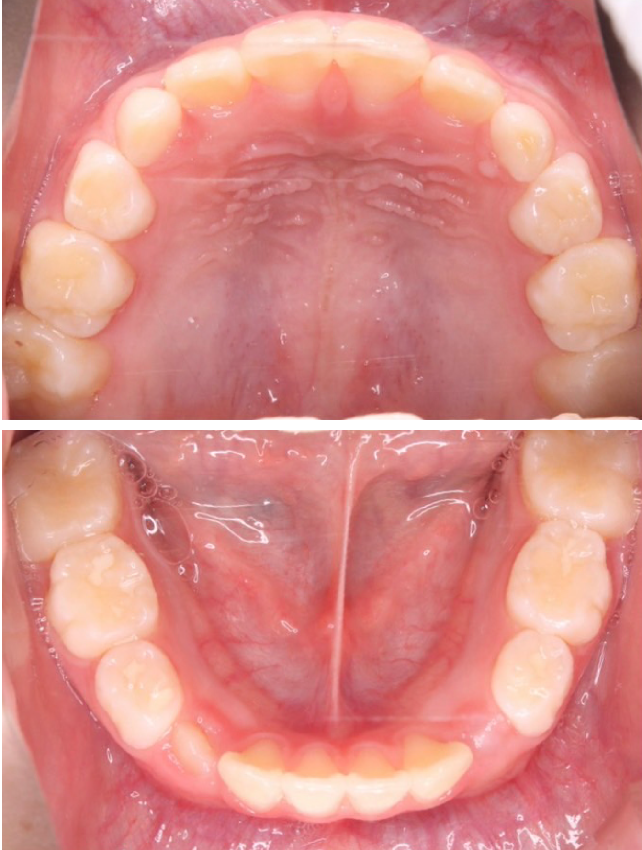

1期治療で使用する装置

拡大床

- 機能

- 横に広げるための装置

- 期間

- 6か月~10か月程度

成長期のお子さまの顎をゆっくりと広げる矯正装置です。顎の成長を正しい方向へ導くことで、歯がきれいに並ぶための土台を整えます。歯を無理に動かすのではなく、顎の成長を活かした治療のため、痛みが少なく、お子さまへの負担が比較的軽いのが特徴です。

拡大床は、多くの場合1期治療の中心となる装置で、将来的な本格矯正の必要性を減らすことにもつながります。 -

当院の症例

CASE